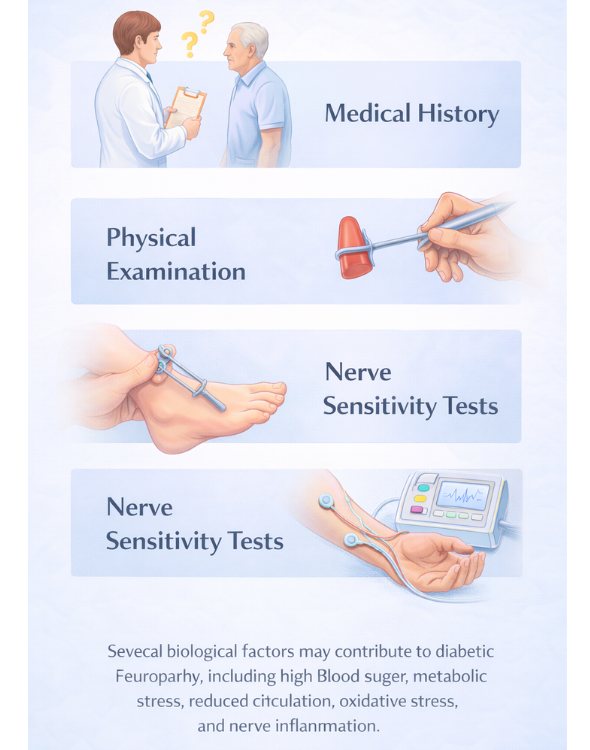

How Diabetic Neuropathy Is Evaluated

Healthcare professionals may evaluate diabetic neuropathy by reviewing symptoms and medical history. In addition, a physical examination may help identify areas where nerve function has changed. Furthermore, diagnostic testing may provide additional insight into how nerve signals travel through the body.

During evaluation, doctors may also examine reflexes, muscle strength, and sensitivity to touch or temperature. Diagnostic tests may also help measure how efficiently nerve signals travel through the body. In this way, healthcare professionals can better observe how nerve communication may be changing.As a result, healthcare professionals can better understand how nerve communication may be changing. In this way, patterns of nerve dysfunction may become easier to identify.